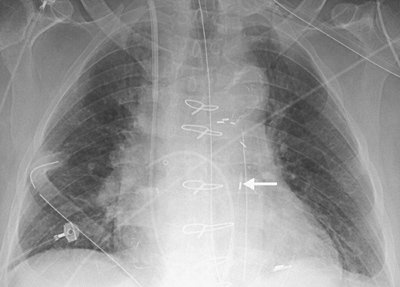

FIGURE 5-8. Hemothorax as a complication of central venous catheter placement. A: PA chest radiograph shows a normally positioned right jugular central venous catheter. B: PA chest radiograph after removal of the right catheter and placement of left subclavian central venous catheter shows a new large left pleural effusion. A chest tube was placed, which drained bright red blood.

Coiling or redundancy of pulmonary artery catheter tubing in the right side of the heart can irritate the myocardial conduction bundle and result in dysrhythmias (Fig. 5-10). Other potential complications of pulmonary artery catheter placement

P.68

include pulmonary artery rupture (leading to pulmonary hemorrhage), pulmonary artery pseudoaneurysm (Figs. 5-11 and 5-12), fistulae between the pulmonary artery and the bronchial tree, intracardiac knotting of the catheter, and balloon rupture (Table 5-2). Complications that can occur with CVP catheter placement can also occur with pulmonary artery catheter placement (Fig. 5-13).